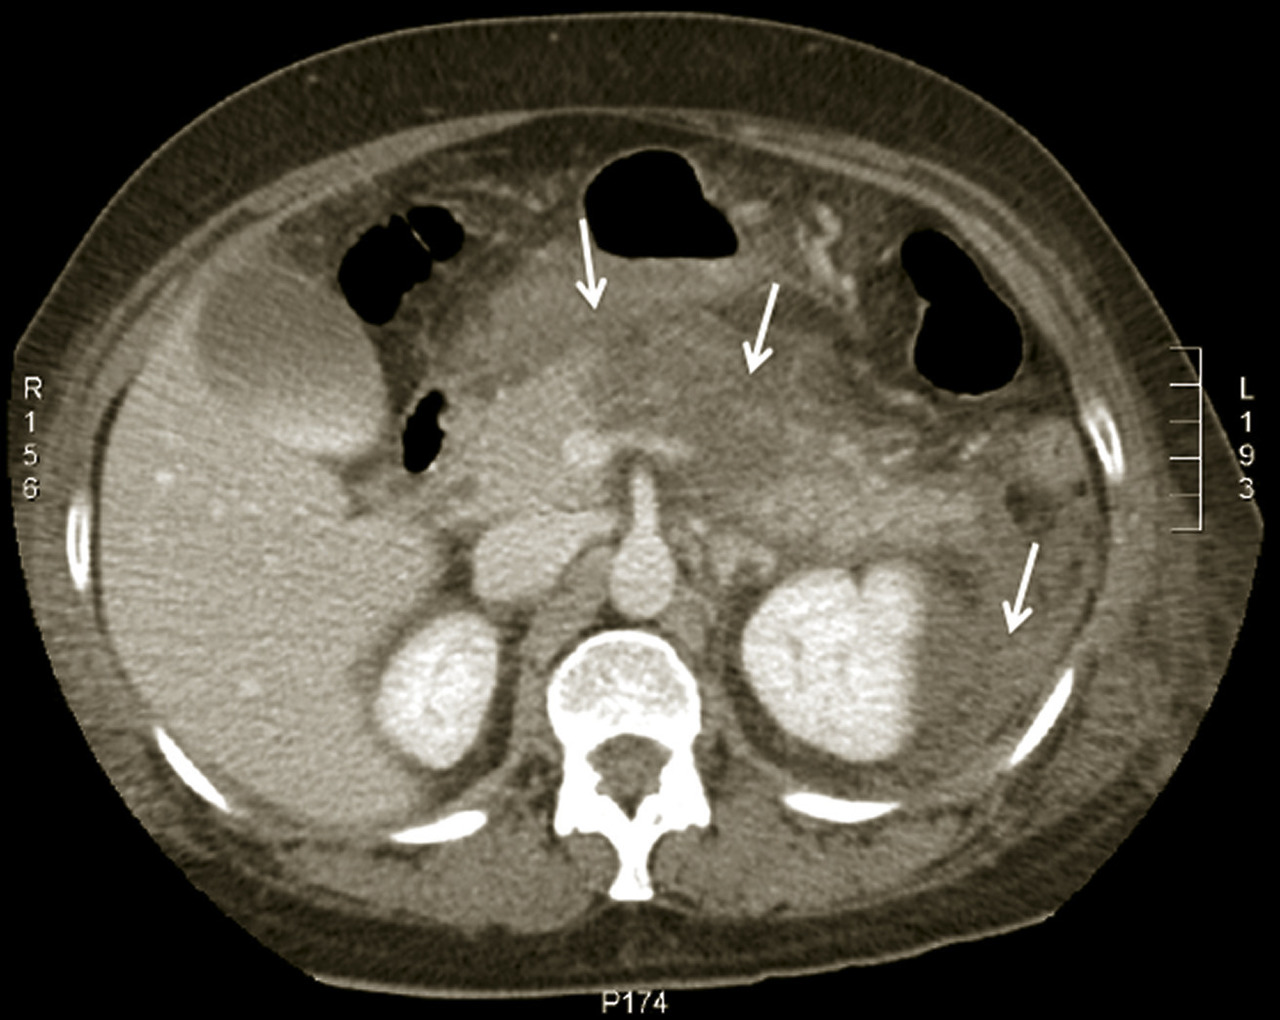

L’échographie abdominale a l’inconvénient d’être opérateur-­dépendante. Ses principales indications sont la lithiase biliaire et ses complications, des douleurs abdominales chez les patients minces et surtout chez la femme pour rechercher une pathologie gynécologique en utilisant le cas échéant des sondes endocavitaires. Ainsi, l’échographie est utile pour affirmer la lithiase biliaire et la cholécystite aiguë (fig. 1) ou objectiver une dilatation de la voie biliaire principale (VBP), rechercher une urétéro-hydronéphrose et des signes indirects en cas de colique néphrétique (fig. 2 et 3), débrouiller le diagnostic des douleurs abdomino-­pelviennes chez la femme.

Le scanner abdomino-pelvien, voire thoraco-abdomino-pelvien, avec si possible injection de produit de contraste iodé (absence de contre-indication, notamment allergie à l’iode, insuffisance rénale sévère et grossesse), s’est progressivement imposé comme moyen d’imagerie diagnostique de première intention grâce à sa précision anatomique, sa rapidité de réalisation, son efficacité diagnostique dans la plupart des tableaux abdominaux urgents à l’exception de la pathologie aiguë annexielle gynécologique. C’est l’examen de choix dans les pancréatites aiguës après 48 à 72 heures d’évolution (fig. 4). L’irradiation et la néphrotoxicité des produits de contraste iodé limitent une application encore plus large chez l’insuffisant rénal, l’enfant, et la femme en âge de procréer (dosage préalable des ß-hCG pour s’assurer de l’absence de grossesse en cours), chez lesquels l’imagerie par résonance magnétique (IRM) abdomino-pelvienne est particulièrement indiquée, mais souvent plus difficile à obtenir en urgence.

Le diagnostic est évoqué devant une violente douleur épigastrique transfixiante, soulagée partiellement par la flexion du tronc (position en « chien de fusil »), une élévation franche de la lipasémie (supérieure à trois fois la valeur normale) et l’imagerie caractéristique au scanner. Deux causes dominent : la migration d’une lithiase biliaire et l’alcoolisation. L’examen clinique est pauvre contrastant avec l’intensité de la douleur et la gravité des signes généraux (marbrures, polypnée, pouls filant, hypotension artérielle). Un premier score de Ranson (clinico-biologique) supérieur à 3 affirme la sévérité de l’épisode. Le scanner (fig. 4), idéalement réalisé après 48 heures, permettra le calcul du score de Balthazar, fortement prédictif d’une complication grave (sur­infection des coulées de nécrose ou décès), en cas de valeur ≥ 4.

L’échographie peut montrer une discrète asymétrie des cavités excrétrices rénales, voire l’obstacle lithiasique avec dilatation d’amont (fig. 2 et 3). L’uroscanner complète le bilan et localise si besoin le calcul. Outre le traitement de la cause (calcul, compression extrinsèque…), le traitement antalgique est primordial : anti-inflammatoires non stéroïdiens (AINS), paracétamol, anti­spasmodiques voire dérivés morphiniques. On procédera à la pose d’une sonde urétérale en cas d’anurie (rein unique), de fièvre sur rétention du haut appareil ou de crise hyperalgique.